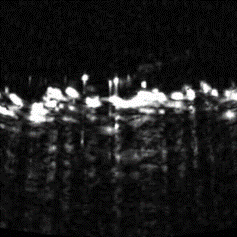

Cross sectional view